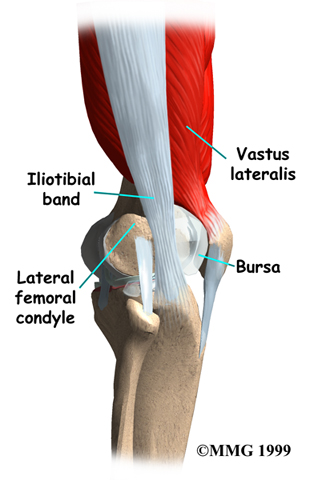

The ITB is actually a long tendon. (Tendons connect muscles to bone.) It attaches to a short muscle at the top of the pelvis called the tensor fascia lata. The ITB runs down the side of the thigh and connects to the outside edge of the tibia (shinbone) just below the middle of the knee joint. You can feel the tendon on the outside of your thigh when you tighten your leg muscles. The ITB crosses over the side of the knee joint, giving added stability to the knee.

The lower end of the ITB passes over the outer edge of the , the area where the lower part of the femur (thighbone) bulges out above the knee joint. When the knee is bent and straightened, the tendon glides across the edge of the femoral condyle.

A bursa is a fluid-filled sac that cushions body tissues from friction. These sacs are present where against one another. A bursa rests between the femoral condyle and the ITB.

Normally, this bursa lets the tendon glide smoothly back and forth over the edge of the femoral condyle as the knee bends and straightens.